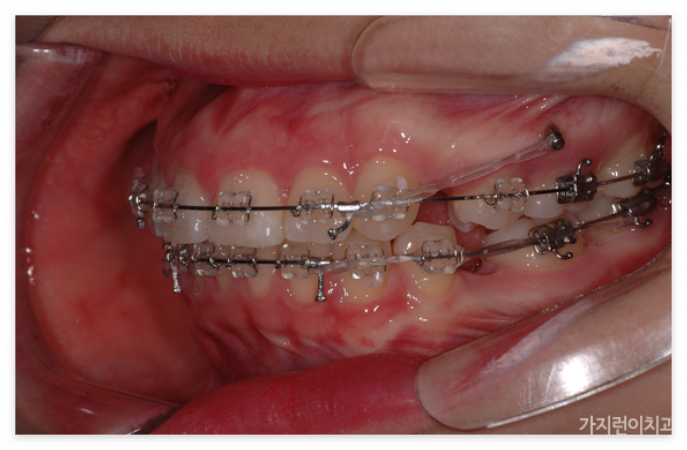

앞으로 돌출된 치아를 구조적으로 안쪽으로 집어넣기 위해서는 공간의 확보가 필요합니다. 그래서 많은 분들이 발치를 진행하는데요. 위와 같은 경우도 상하악 제1소구치를 발치한 후에 충분한 공간을 확보한 후에 진행을 하였습니다. 특히 발치가 무조건 안 좋고 비발치가 좋은 것이라고 오해하는 경우가 있는데 발치할 케이스임에도 비발치로 진행하게 되면 오히려 더 안 좋은 결과를 안아볼 수 있기 때문에 상악 전치의 후방이동을 위한 충분한 공간확보를 위한 과정이라고 이해하면 되겠습니다. 본원에서는 서울 거미스마일 교정을 위해 미니스크류를 식립해 상악 전치를 위로 올리는 힘을 추가 했습니다. 미니스크류를 이용하면 개선할 충분한 힘이 가해지기 때문에 상하악 전치가 동시에 이동할 수 있습니다.